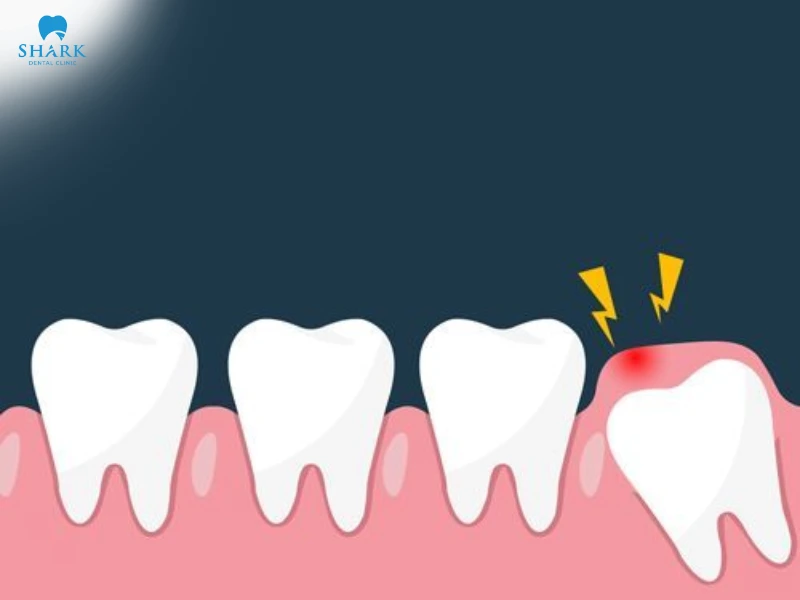

- Lợi bị sưng đỏ ngay chính giữa răng khôn. Phần lợi trùm và bao bọc xung quanh răng khôn

- Lợi sưng tấy, có mưng mủ, chảy máu và đau nhức

- Lợi trùm răng khôn gây sốt cao, khó chịu, tác động đến quá trình vệ sinh và ăn nhai

- Miệng bị hôi do răng khôn bị lợi trùm viêm nhiễm, vi khuẩn tích tụ nhiều dưới chân răng.